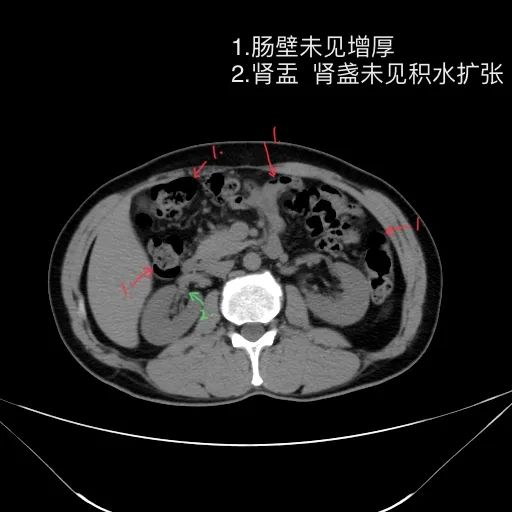

影像描述:

肝脏缩小,包膜凹凸不平,肝裂增宽,各叶比例失衡,肝实质密度不均,肝S4小片低密度影,约cm;胆囊不大,其内未见异常密度影,胆道系统未见扩张;胰腺、脾脏形态、密度、大小未见异常;双肾上腺及双肾形态、密度、大小未见异常,双输尿管未见扩张,膀胱充盈良好,壁光滑,其内未见异常密度影;前列腺未见异常;胃肠道未见充盈,壁未见明确增厚,食管胃底多发迂曲、增粗血管,腹部及腹膜后未见肿大淋巴结;腹水。